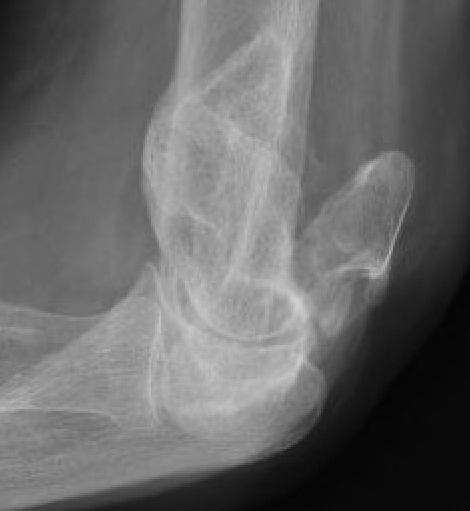

Bag of bones / nonoperative management

Initial injury in elderly patient

Elbow post treatment in cast

Indication

Patient elderly and not operative candidate

Technique

Initial rest in plaster then mobilisation

Results

- 40 "elderly and low demand" patients treated non-op

- 5 year mortality 40%

- 50% non union

- DASH score 38/100

- modest function, but avoids risks